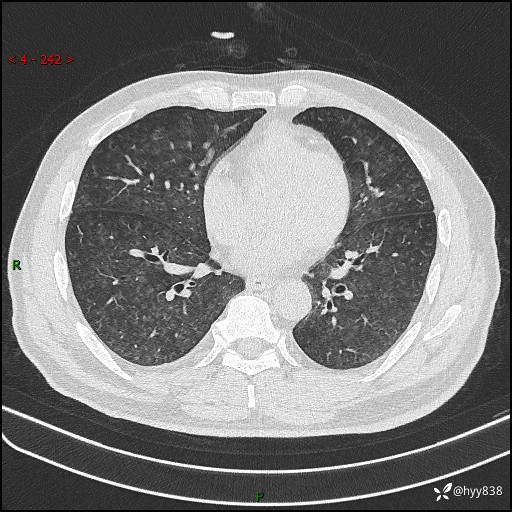

昨天肺结节门诊,“对门”呼吸科申请会诊病例,弥漫性肺部病变---结果公布~

患者年龄:51岁

主诉:发热、咳嗽、咳痰1周

简要病史:患者1周前无明显诱因出现咽喉部疼痛,随后出现咳嗽咳痰,起初干咳为主,后出现咳少许绿色痰,当时有发热,体温为39℃,无畏寒寒战,无胸闷胸痛,无活动后气短,无咯血,无鼻塞流涕,无全身酸痛,患者于诊所输液治疗后体温正常,但仍有咳嗽。患者3天前当地县人民医院就诊,患者仍有咳嗽,咳嗽较为频繁,咳嗽后出现头痛,伴有少许咳痰,随后出现活动后气短,1天前患者再次出现发热,体温最高为40℃,伴有畏寒寒战,伴有乏力、纳差,伴有胸闷不适,无咯血,无全身皮疹,无血尿、尿频尿急尿痛,无腹泻,诊断为“重症肺炎 感染性休克 肾功能异常 痛风”;予以抗感染(亚胺培南),抗病毒(奥司他韦)等对症治疗。患者复查胸部CT提示双肺病灶较前有所增多,建议上级医院就诊,门诊以“肺部感染”收入我科。 起病以来,患者食欲欠佳,大小便正常,睡眠、精神欠佳,体力下降、体重无明显变化。

辅助检查:CT

临床诊断:肺部感染

胸部HRCT